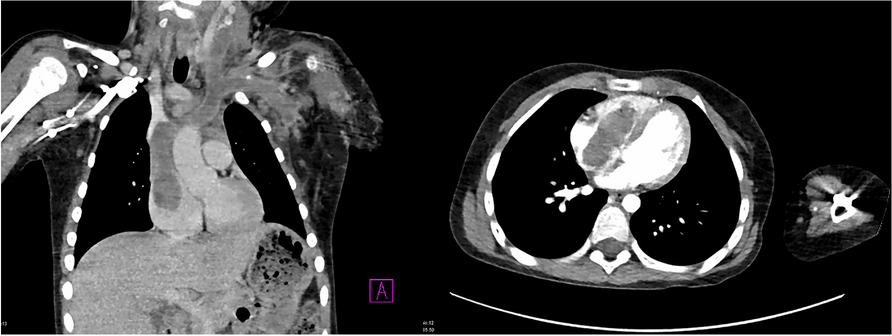

In this specific case, the patient, affected by L. Pneumophila, presented a PO2/FiO2 ratio between 100mmHg and 200mmHg, giving rise to a moderate ARDS panel according to Berlin Criteria (Image 1).

For this reason, we decided to use a non-invasive periprocedural ventilation mode, specifically the High Flow Nasal Cannula (HFNC), to reduce the risk of postoperative pulmonary complications due to invasive ventilation through endotracheal intubation (ETI).

Image 1 (abstract A9).

See text for description

Bild vergrößern